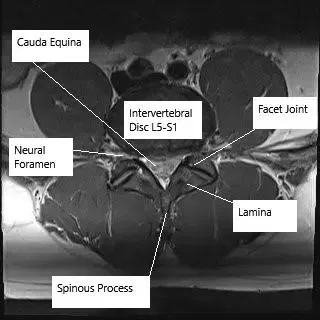

MRI image in axial section showing lumbar spine at the level of L5-S1.